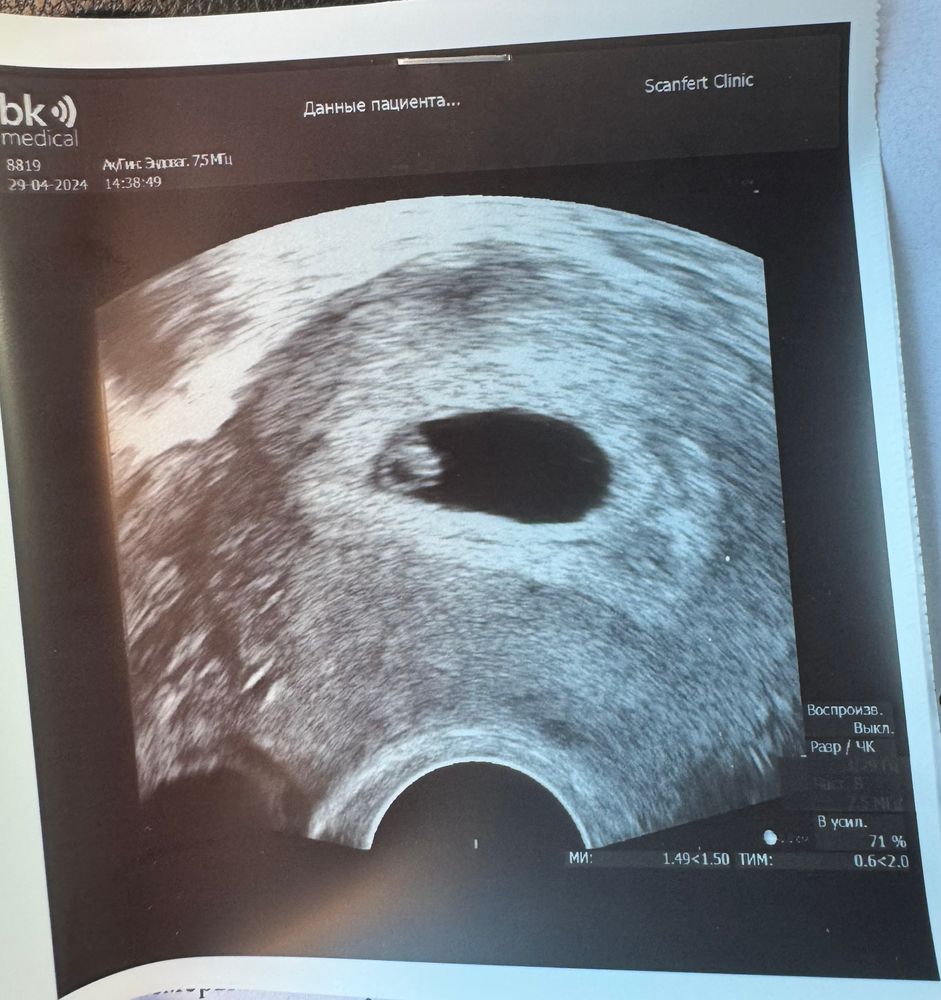

16дпп УЗИ ПЯ 7*9, ЖМ 1,9

26дпп УЗИ ПЯ 23, КТР 4,7 мм, ЖМ 4,1, сб+